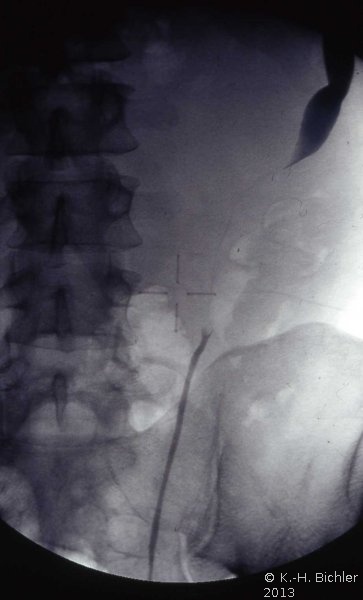

Das Ausscheidungsurogramm ergab eine stumme Niere links (Abbildung 18c). Die retrograde Sondierung zeigte eine deutlische Kompression des Harnleiters sowie eine verkleinerte Niere links mit destruierten Kelchen (Verplumpung) (Abbildung 18d).